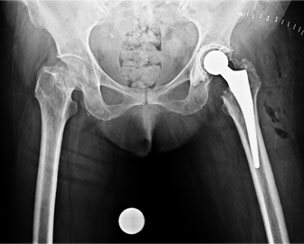

Post Total Hip Replacement

The xray picture after total hip replacement. The socket (acetabular cup) was fixed with bone cement whereas the femoral stem is uncemented. The length of the limb has been restored.

2 months after THR

2 months on the patient is walking well.